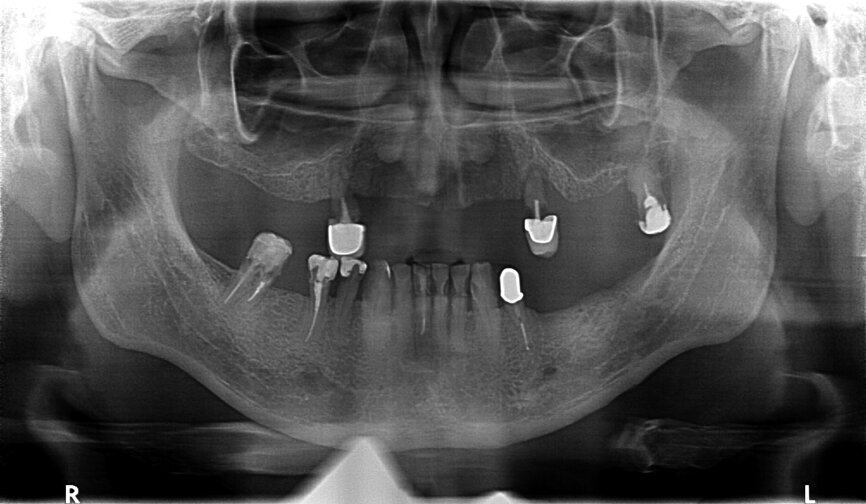

Fig. 29: OPG prior to treatment.

Fig. 30: OPG after placing implants.

Fig. 31: OPG after exposing implants at the lateral section and having used a temporary prosthesis based on telescopes.

Fig. 32: OPG after treatment.

If the quality of the work satisfies our expectations, we may proceed to the handing-over stage and perform the functional and aesthetic analysis, both intra- and extraorally. A perfect conclusion to the treatment process is the receipt of a complete set of OPG X-rays taken before, during and following treatment (Figs. 29–32).